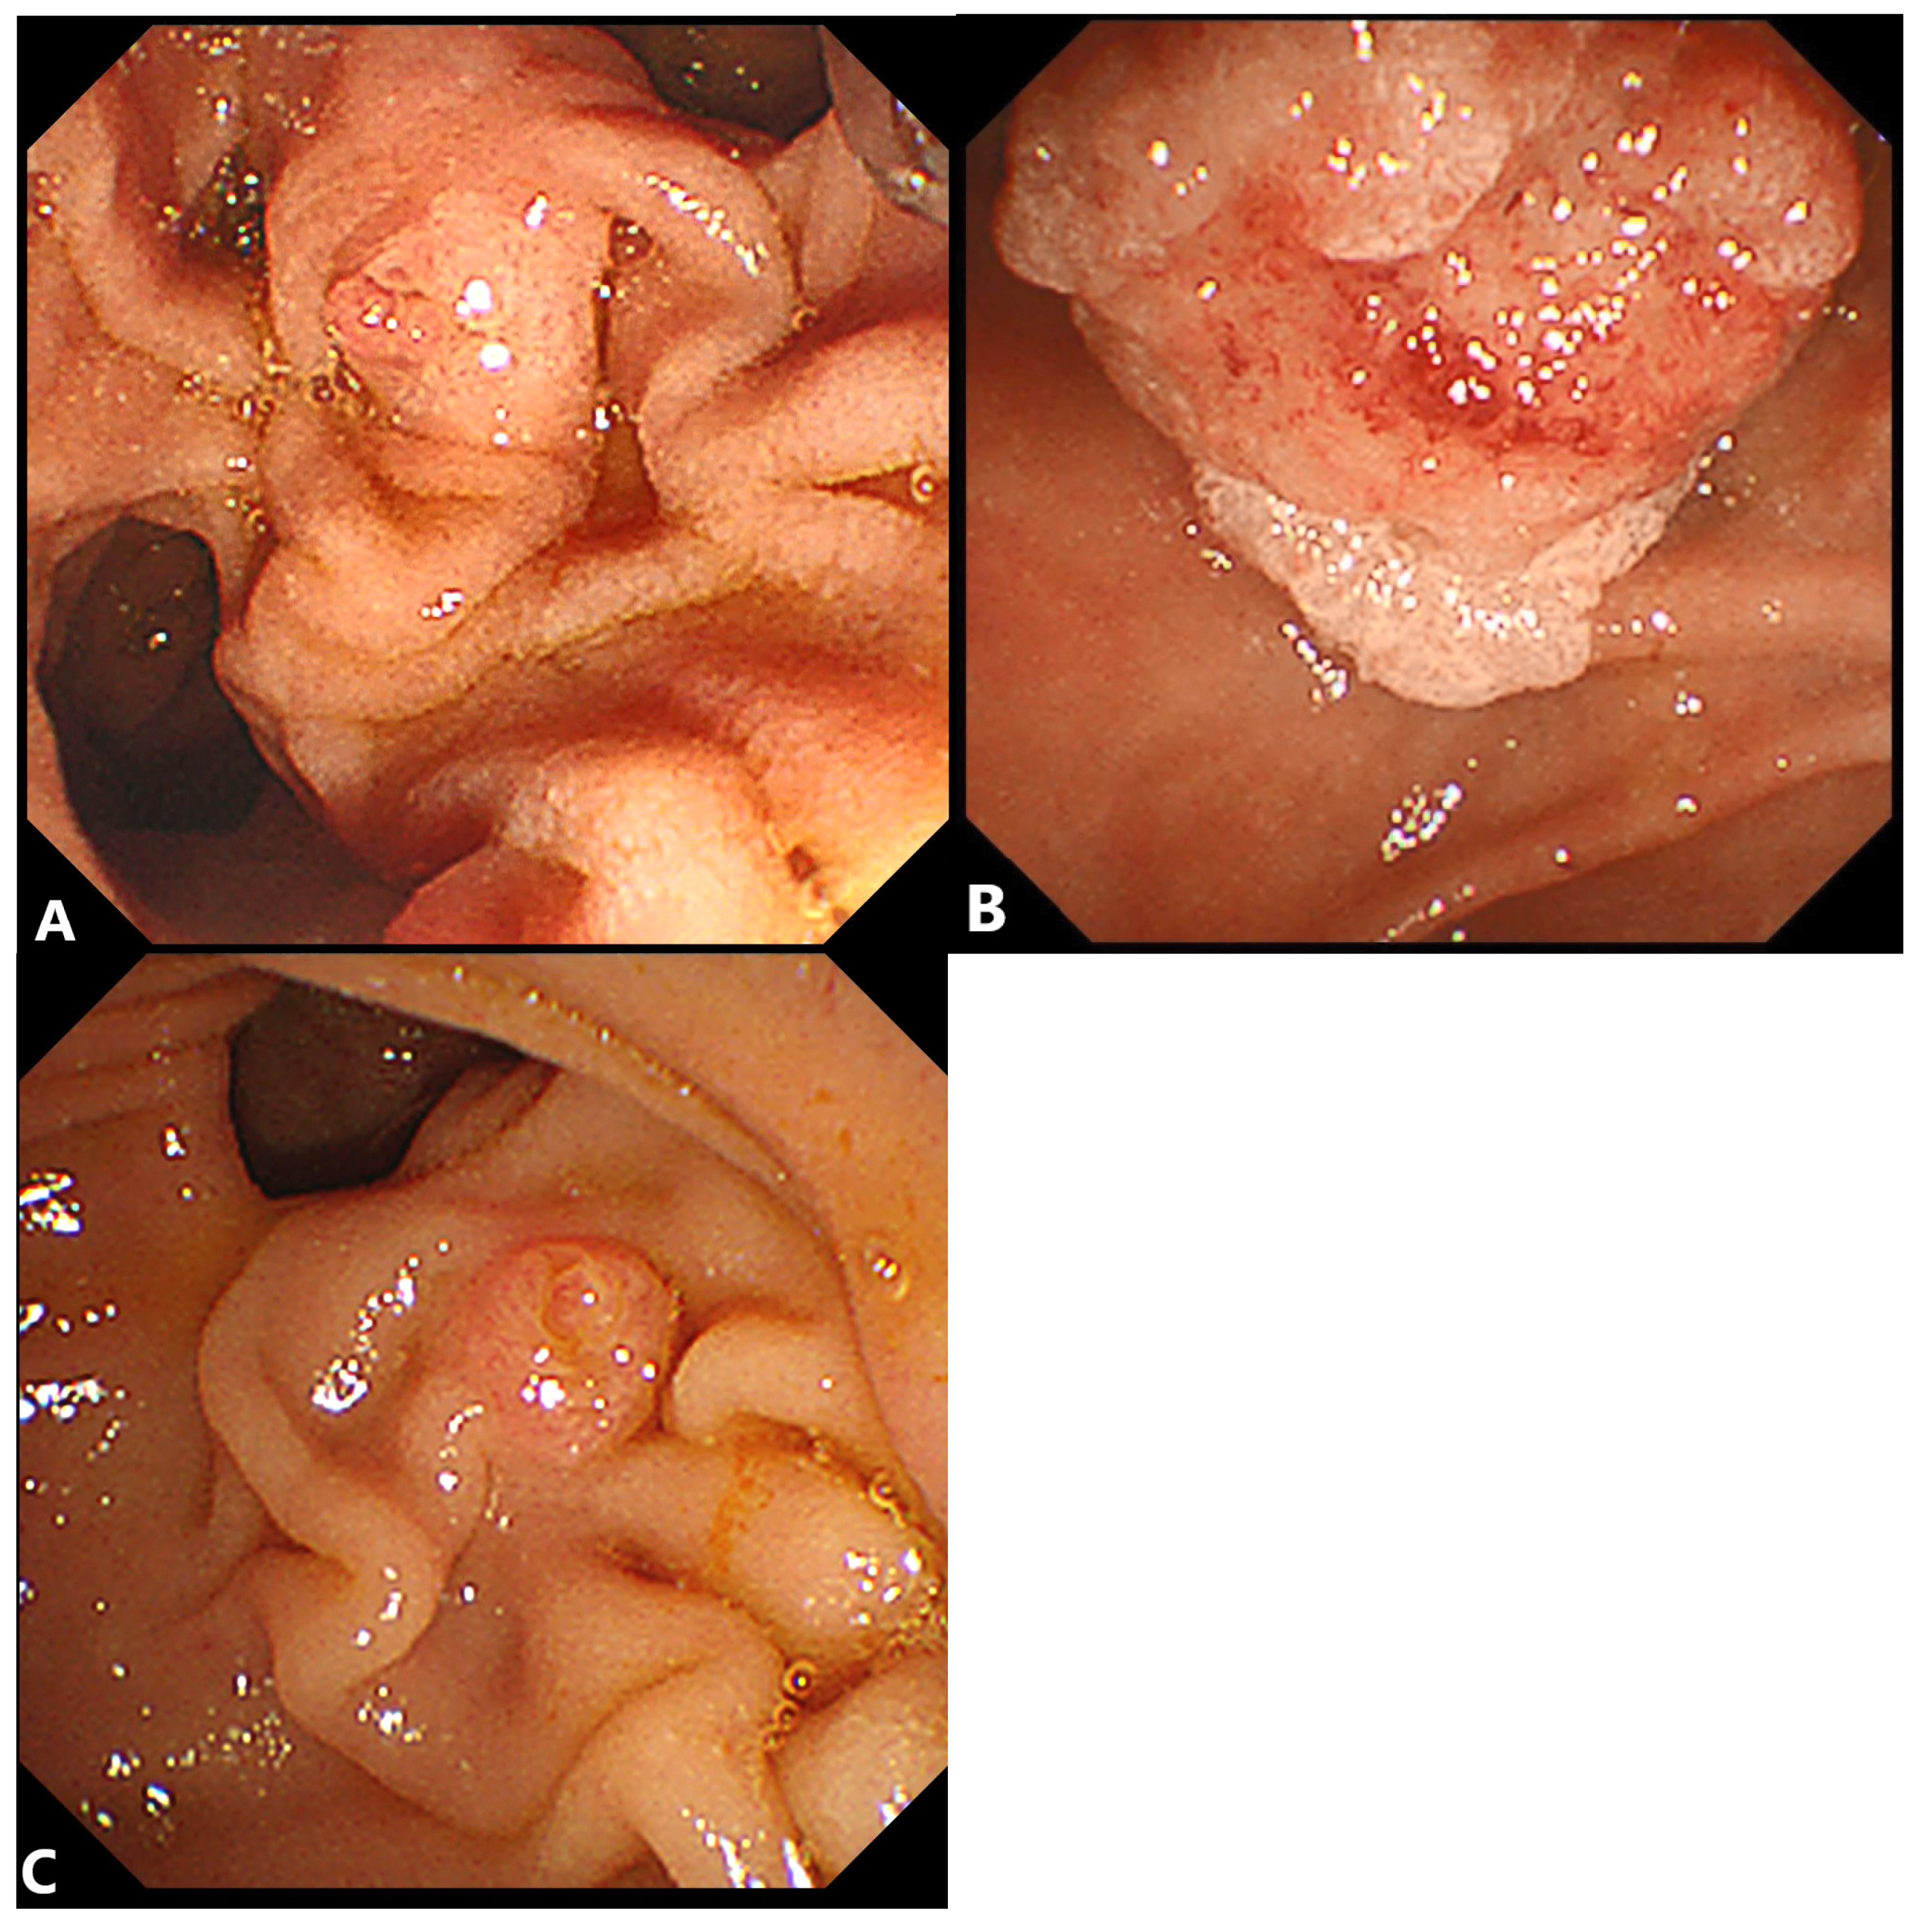

2.1. Double-Guidewire (DGW) Technique with or without Pancreatic Stenting